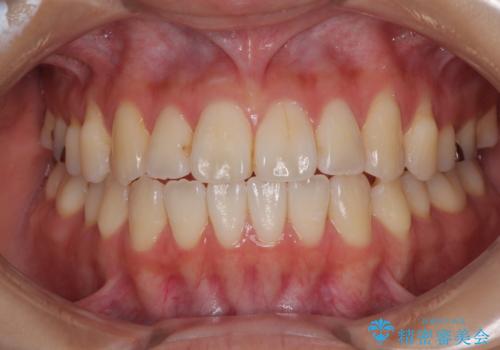

舌の突出癖が原因 インビザライン矯正による開咬改善

開咬の治療は、前歯を閉じるように動かすとともに、上下臼歯を圧下(骨内にめり込ませる)させることで進めて行きます。

インビザラインは臼歯の圧下を効果的に行えるため、インビザラインを用いて矯正治療を行うこととしました。

オープンバイトは舌の突出癖により誘発され、治療後も突出癖が残っている容易に後戻りしてしまいます。

治療期間を短縮するためにも、舌突出癖の改善が極めて重要となります。

特にインビザラインではIPRという歯と歯の間を削る処置を多用するため、後戻りによりスペースが生じやすくなるため、治療初期段階での舌のトレーニングが必須となります。